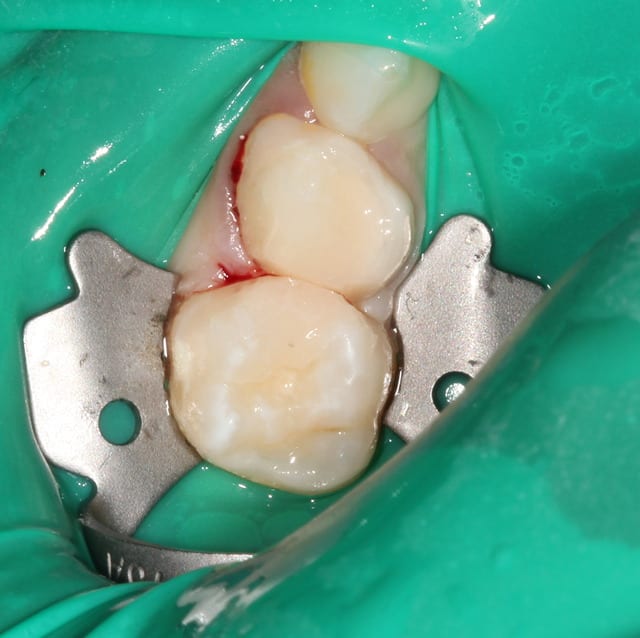

Oui. Les coins surtout sont parfaits car ils sont assez compressifs pour stopper tout saignements proximal, très fréquents chez l'enfant.

Je fais les compos sur dents de lait de la manière la plus rapide possible (adhésif automordançant, entre 1 et 3 apports successifs de composite, morphologie simple du moment qu'il y a un point de contact correct ça me va).

Du moment qu'il y a une matrice, que le bord proximal est propre et qu'il y a un coin interdentaire, la cavité reste sèche pendant une minute le temps de faire l'obturation et ça tient très bien (plusieurs années).

Je soigne exclusivement des enfants et toujours sous digue. Comme je te le disais plus haut : cela ne prend pas plus de 30 secondes et ce temps "perdu", tu le regagnes largement derrière.